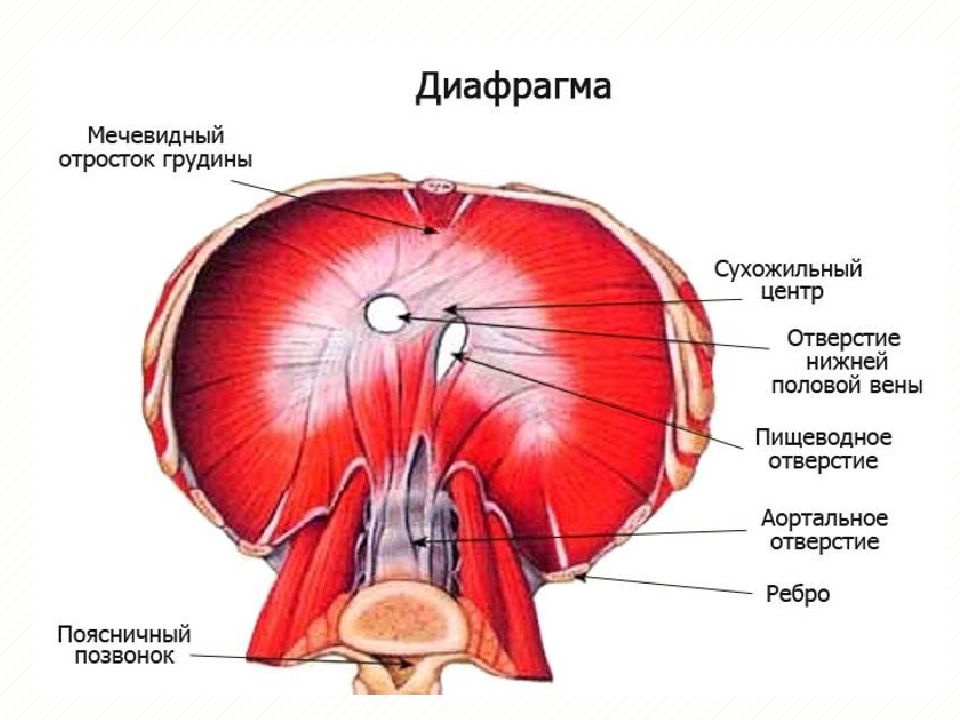

Анатомия диафрагмы и треугольника Бохдалека

Раздел: Визуальный дайджест